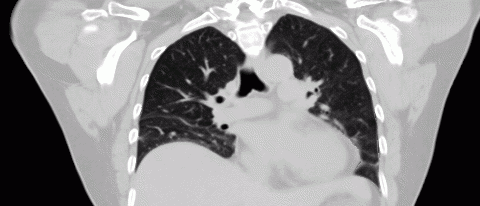

Accurate time-resolved imaging is crucial to the management of respiratory motion in radiation therapy treatment planning. Conventional techniques for producing breathing gated images commonly suffer from artifacts due to their inability to account for irregular breathing cycles. A novel CT acquisition and analysis technique, 5DCT, is utilized at UCLA in order to better inform treatment plan design for mobile tumors. Compared to current commercial protocols, 5DCT offers several advantages:

5DCT exploits standard fast helical acquisition with simultaneous breathing surrogate measurement, deformable image registration, and a breathing motion model to remove sorting artifacts. The accuracy of the motion model is assessed by reconstructing the original fast helical scans, which provide a ground truth.